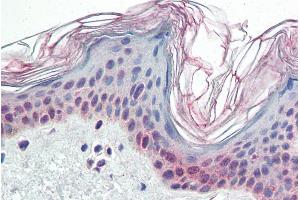

PARP2 Reactivité: Humain WB, ELISA, IHC Hôte: Lapin Polyclonal unconjugated

N° du produit ABIN2148455

741,44 €

Plus frais de livraison 40,00 € et TVA

100 μg

Destination: France

Envoi sous 13 à 17 jours ouvrables